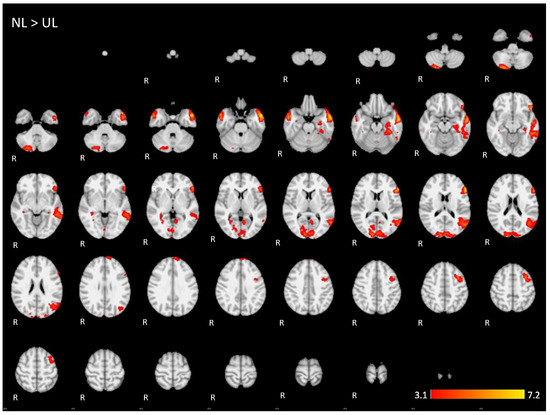

Appendix A. The 2D fMRI Maps of All Brain Slices for Both Active Conditions (NL, UL) and for Both Contrasts (NL > UL and UL > NL)

| NL > UL | 6.47 | −58 | 28 | 14 | Left inferior frontal gyrus, pars triangularis |

| 4.93 | 14 | −92 | 14 | Right occipital lobe/cuneus | |

| 4.72 | −56 | −70 | 14 | Left middle temporal gyrus | |

| 5.01 | 26 | −82 | −46 | Posterior lobe of right cerebellum | |

| 4.87 | −36 | 8 | 48 | Left middle frontal gyrus | |

| 5.33 | 54 | 0 | −26 | Right middle temporal gyrus, anterior division | |

| 4.36 | −6 | 62 | 34 | Left superior frontal gyrus | |

| 4.14 | −6 | −58 | 6 | Left precuneus cortex | |

| 3.98 | 34 | −36 | −2 | Right hippocampus | |